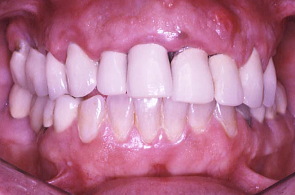

初診時の口の中の状態、歯ぐきは赤く腫れている。特に上の歯肉全体が浮腫して歯肉の締まりがなくなっている。